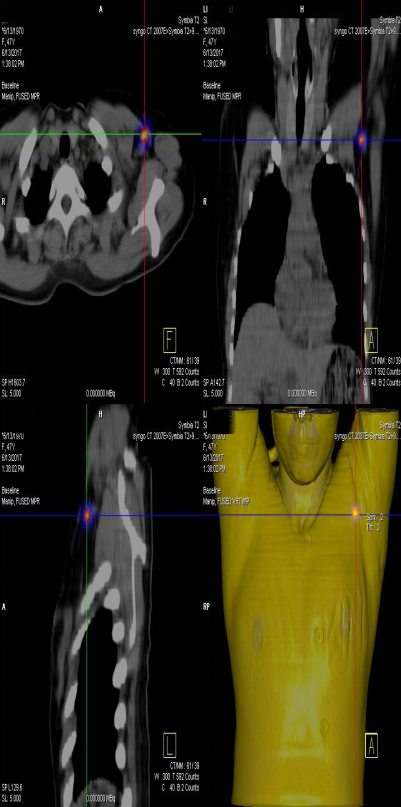

前哨淋巴結顯像技術一般在腫瘤附近注射放射性核素標記特殊藥物,這種藥物會被前哨淋巴結攝取,存在于前哨淋巴結中。24小時之內(nèi)都可用SPECT-CT進行前哨淋巴結顯像檢查。

患者李女士,發(fā)現(xiàn)右側乳腺腫物,來我院就診,行乳腺腫物局部擴大切除術,術后病理回報:右乳腺浸潤性導管癌III級,伴原位癌。擬行右乳腺癌切除術,提檢前哨淋巴結顯像檢查,明確有無淋巴結轉移。